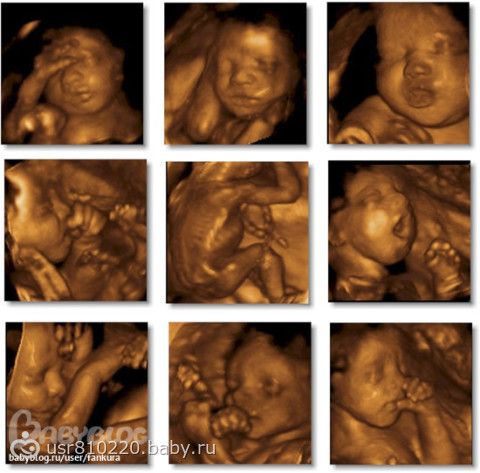

хотелось бы что бы качество изображения было четкое и цветное (желтого цвета, не знаю как правильно называется)

хотелось бы вот такого изображения!!! такое делают в тонусе?

В тонусе мне делали узи уже на 32 вроде неделе, там конечно в желтеньком цвете по телевизору было, но напечатали в черно-белом и всего 2 фотки не очень четкие, дочка крутилась и дралась с  врачом))) Может стоит съездить в диагностический центр в платный отдел? Цена та же будет, что и у нас в городе, но может качество обслуживания лучше будет???

а в тонусе на каком сроке была? тебе фотку чернобелую дали? или желтенькую? просто на желтенькой лицо видно лучше